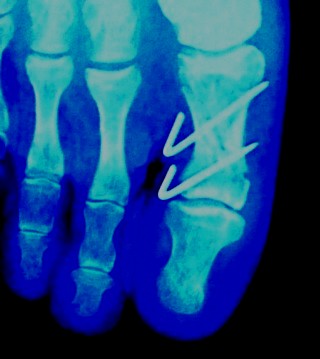

12月30日に撮ったレントゲン写真。

ピンは抜けていますが、まだ亀裂がわかりますね。

これからリハビリをしますが、決して無理をするな、と言われました。

急に体重をかけると、パキンと割れることがあるとのこと。